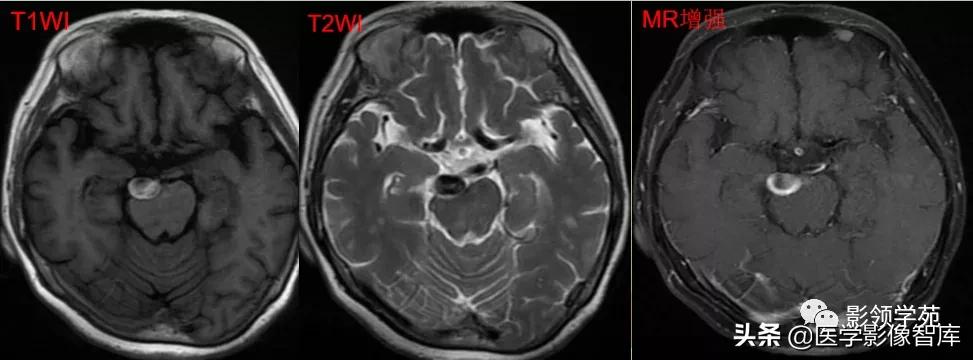

女 72岁,发现糖尿病3年余

鞍上区见一团块状稍高密度影,边界尚清,密度均匀。

鞍上右上方见一类椭圆形流空影。

病灶明显强化(瘤内血栓未强化),边界清楚,与右侧颈内动脉海绵段分界不清。垂体大小、形态未见异常。